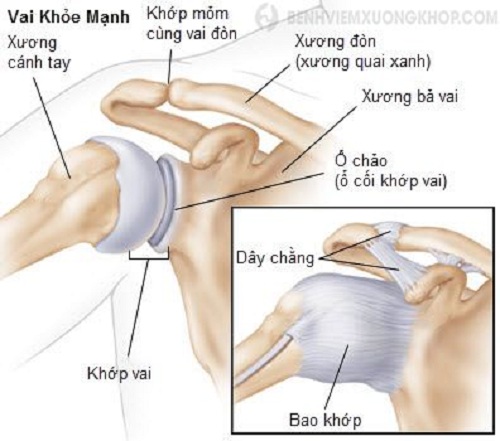

Glenohumeral ligament: анатомия и функции плечевого сустава